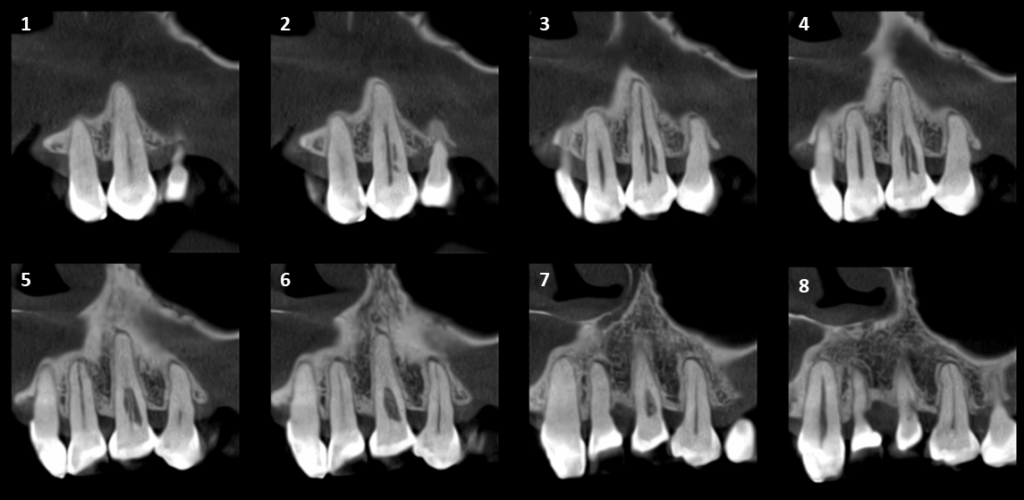

En la tomografía computarizada de haz cónico se identifica en la pieza 23 una imagen isodensa que compromete las paredes radiculares mesial, distal y palatina a nivel del tercio cervical, en estrecha proximidad con el conducto radicular. Asimismo, se observa un ensanchamiento del espacio del ligamento periodontal adyacente.

CORTES AXIALES

CORTES TRANSAXIALES

- Reabsorción cervical externa en pieza 23.